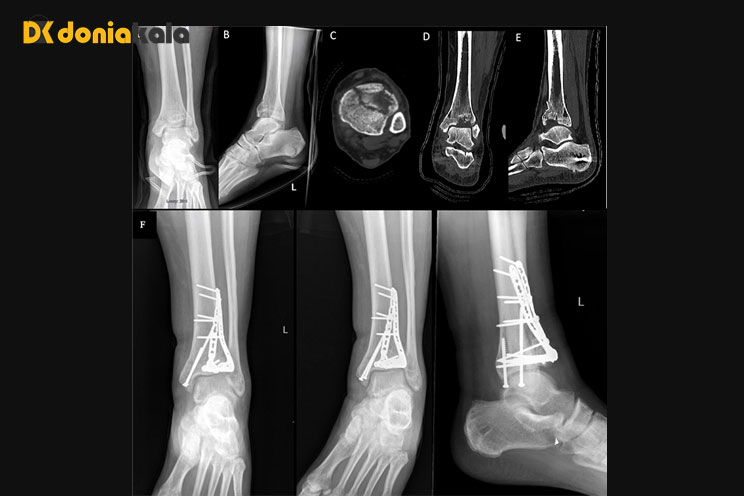

جراح شما از صفحات و پیچ های فلزی در استخوان استفاده می کند تا استخوان ها را در موقعیت صحیح نگه دارد. بسته به میزان جراحات شما، جراح ممکن است این کار را در 2 جراحی جداگانه انجام دهد. پس از بهبود اندکی پای شما، جراح ممکن است یک بریس یا آتل متحرک برای شما تجویز کند تا هنگام برداشتن آن بتوانید فیزیوتراپی انجام دهید. این تمرینات به بازیابی و حفظ دامنه حرکتی و قدرت شما کمک می کند. شما باید چندین ماه پس از آسیب دیدگی از عصا استفاده کنید. جراح شما همچنین ممکن است دارویی (رقیق کننده خون) برای جلوگیری از لخته شدن خون در پای شما در حین بهبودی تجویز کند. همچنین ممکن است دستورالعمل هایی را در مورد رژیم غذایی به شما ارائه دهد، مانند اطمینان از اینکه رژیم غذایی حاوی کلسیم، ویتامین D و پروتئین زیادی دارید. ممکن است از شما بخواهد که برخی از انواع داروهای بدون نسخه را برای درد مصرف نکنید. این به این دلیل است که اینها ممکن است در بهبود استخوان اختلال ایجاد کنند. اگر سیگار میکشید، پزشک شما را تشویق به ترک سیگار کند، زیرا این امر میتواند در بهبود استخوان نیز اختلال ایجاد کند.